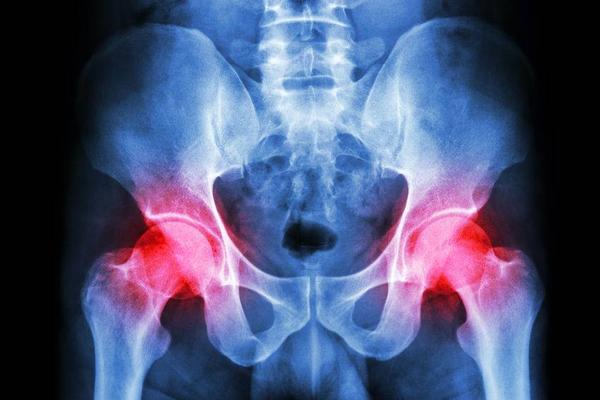

胯骨在医学上指的就是髋关节,它连接下肢和躯干,骨盆和股骨,承担着上半身的重量,和日常的行走站立有着密切的联系。

髋关节可以说是身体上最大的关节结构复杂,而且有很多的韧带,肌肉和软组织。

正常情况下,胯骨并不会有疼痛的感觉,可若是近期一段时间总是无缘无故的疼痛,一定要重视起来,临床调查数据显示,胯骨疼痛多是以下5个因素所导致。

2、髋关节炎

髋关节炎症患病的早期症状不是很明显,但是随着病情不断发展,髋关节就会有僵硬,肿胀,酸痛等症状,有时甚至还会限制活动,而导致髋关节炎的主要因素就是身体肥胖。